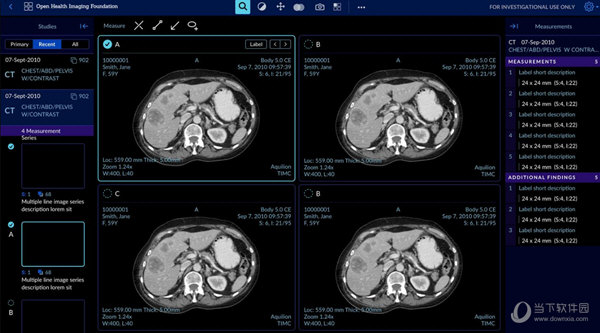

6、多系列观赏:可以在多个面板中同时打开多个系列的一个或多个研究用于比较。